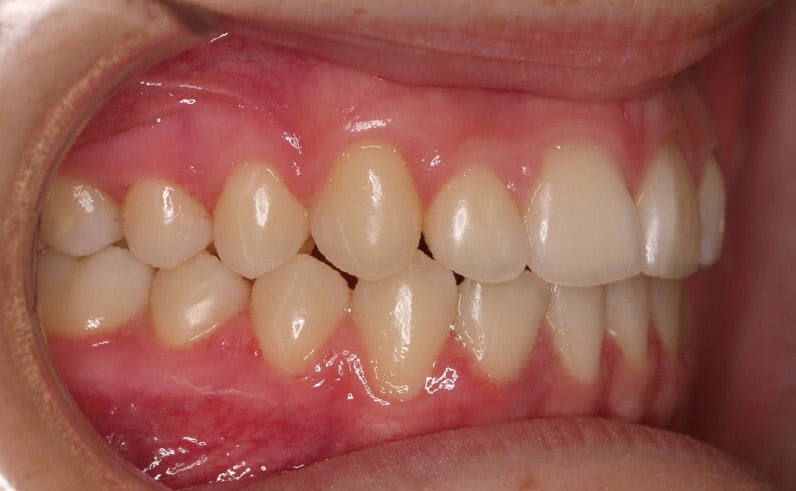

La paciente O.O. acude a nuestra consulta por:

– Canino 13 e incisivo lateral 42 en posición ectópica.

– Canino 23 incluido.

Con lo que decide realizarse un tratamiento de ortodoncia de duración de 24 meses con brackets damon Q.

CASO COMPLETO: